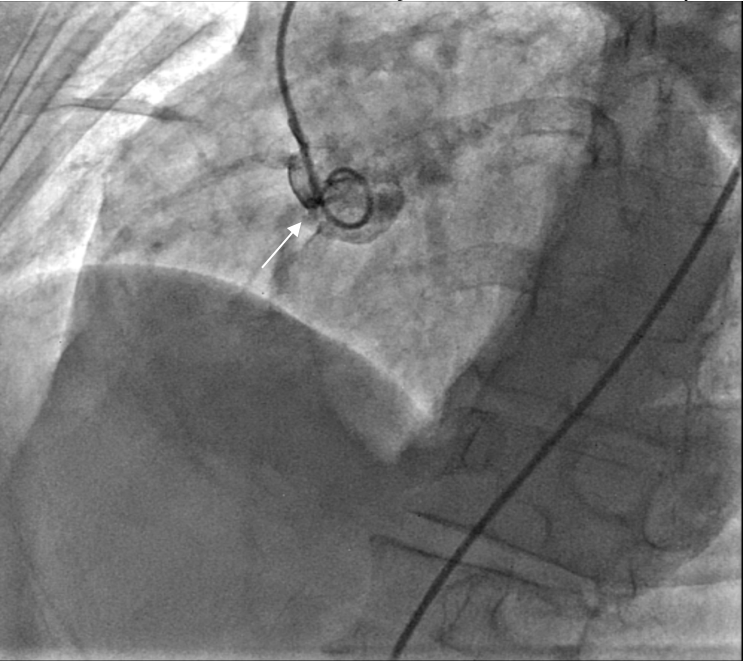

Sizing of the lesion was conducted under fluoroscopy and by using periprocedural echo, and determined to be 4 mm. A multipurpose catheter and Glidewire (Terumo Interventional Systems) was used to cross the defect. Another multipurpose catheter was introduced via the venous approach, through which the antegrade wire was snared in the pulmonary artery. The wire was then externalized, leading to the formation of an arteriovenous rail (Figures 2A-B, Videos 2A-B).

Figure 2A. Snaring of the wire.